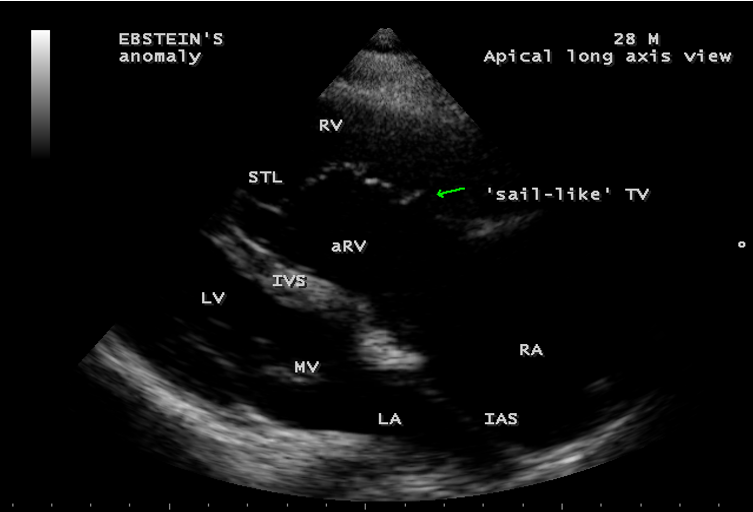

A 28-year old male presented with cyanosis and auscultation revealed a ‘sail sound’ ( loud tricuspid component of first heart sound due to increased tension developed by the large anterior leaflet as it reaches the limits of its systolic excursion- an important sign of anterior leaflet mobility), a ‘cadence’ quality of quadruple rhythm due to wide splitting of first and second sounds ( due to complete right bundle branch block), atrial and ventricular filling sounds (summation of these sounds due to prolonged PR interval). ECG revealed the features of Ebstein’s anomaly as shown in Figures 11 and 12. X-ray chest revealed the Ebstein’s configuration as shown in Figure 13. 2D echocardiography revealed a ‘sail-like’anterior tricuspid leaflet forming a ‘muscular curtain’ in between the inflow and trabecular parts of the right ventricle as an ‘imperforate membrane’ with a ‘pinhole’communication, associated with a muscular VSD (ventricular septal defect) in the proximal, atrialized compartment of right ventricle suggesting an ‘atretic” (‘imperforate’) Ebstein’s anomaly as shown in Figures 14 to 27.

Echocardiographic features Echocardiography is the diagnostic test of choice for Ebstein’s anomaly and the first echocardiographic diagnosis was reported by Lundstrom in 1969. The first diagnostic criteria for Ebstein’s anomaly using a multi-crystal two-dimensional system was defined by Hagan in 1974 [33] and they were able to recognize the apical displacement of the septal tricuspid leaflet and an elongated anterior tricuspid leaflet with increased excursion. The septal leaflet of the tricuspid valve attaches chiefly to the ventricular septum , but part of its basal attachment is to the posterior wall of the right ventricle [34] and it normally exhibits a slight but distinct apical displacement of its basal attachment to the central fibrous body compared to the mitral valve. The distal displacement of septal origin of tricuspid valve seems to be the best echocardiographic criterion as the characteristic sign for Ebstein’s anomaly and the degree of maximal displacement in normal hearts varies considerably with a mean difference of approximately 6 mm with mitral valve. To define the anatomic severity of Ebstein’s anomaly, four-chamber view is the best to demonstrate the apical displacement of septal tricuspid leaflet [35]. The ratio between the mitral-to-apex distance and the tricuspid-to-apex distance varies from 1 to 1.2 in normal subjects and 1.8 to 3.2 in patients and it is 3.6 as in Figure 18 with Ebstein’s anomaly. The true distance in the level of insertion of atrioventricular valves is obtained by substracting the tricuspid-to-apex distance from the mitral-to-apex distance with a mean value of 27.25 ± 12 mm in patients with proven Ebstein’s anomaly and it is 60 mm as shown in Figure 18 compared to reference group (5.7 ± 2 mm). Kambe and coworkers calculated the distance between both atrioventricular valves directly as a mean value of 21 mm with a range of 14 to 32 mm [36]. A maximum difference in the level of valve insertion of >15 mm in children and >20 mm in adults is discriminated between normal and Ebstein’s anomaly [37],[38]. Despite this fact, a patient with an ‘unequivocal’ Ebstein’s malformation can be encountered in whom the diagnosis cannot be made with certainity solely on the basis of apical displacement of the septal tricuspid valve leaflet. Occasionally, the leaflet attaches to the trabecular part rather than the inlet part of the septum, the conventional four-chamber view will not reveal any septal insertion as shown in Figures 28 and 29.

The anterior tricuspid leaflet is not involved in the process of downward displacement, it may be abnormally inserted occasionally and Shiina, et al documented the apical displacement of anterior tricuspid leaflet in 14% of cases echocardiographically [39]. The anterior leaflet forms a large, sail-like intracavitary curtain as in Figures 14, 25 and contains muscular strands instead of consisting entirely of a fibrous membrane as in the normal tricuspid valve [40]. It is potentially mobile with a brisk sail-like movement as shown in Figure 21 to 24 [41], free bloating with a ‘whipping motion’ across the right ventricular outflow tract (RVOT) as shown in Figure 26 and in some cases, the movement is restricted due to its adherence to the ventricular wall as in Figure 1 and 2, 4 and 9. It is often fenestrated, may in part be musculaized , inserting into the trabeculations of the right ventricle (RV) as in Figure 28 and rarely, the anterior leaflet forms an ‘atretic’ membrane that spans the midportion of the right ventricular cavity as in Figure 16.

Ebstein’s original case was an example of obstruction at the tricuspid orifice by a membrane dividing the right ventricle into two halves as shown in Figure 16 of a 28-year old cyanotic male with ECG and X-ray characteristics as in Figure 11 to 13. suggesting an advanced spectrum of Ebstein’s malformation , necessitating RV exclusion techniques such as Starnes’ procedure. The florid case of Ebstein’s anomaly with the insertion of leaflet tissue along with ventricular walls as a ‘blanket’ as in Figures 28 and 29 in a 30-year old cyanotic male may go for an initial palliation with bidirectional Glenn shunt (cavopulmonary anastomosis). The other variants of moderate degree of leaflet tethering with varying degrees of regurgitation, but an intact basal leaflet attachments with atrioventricular junction as in Cases 1 and 2 may need a definite repair. In Ebstein’s mitral valve as in Figure 32 in a 10-year old boy, the downward displacement of functional annulus > 0.8 cm/m2 is not particularly striking and tends to affect the septal leaflet (anterior mitral leaflet) alone. The valve is thickened and mildly regurgitant due to rheumatic involvement rather than an anatomic cause.